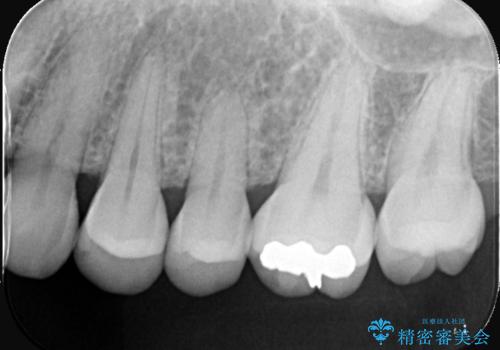

- クリーニング希望で来院されました。お口の中を確認したところ虫歯があり、部分的な詰めものでの修復となりました。材料の性質を説明し、セラミックインレーを選択されました。

接着時にはラバーダム防湿を行っています。